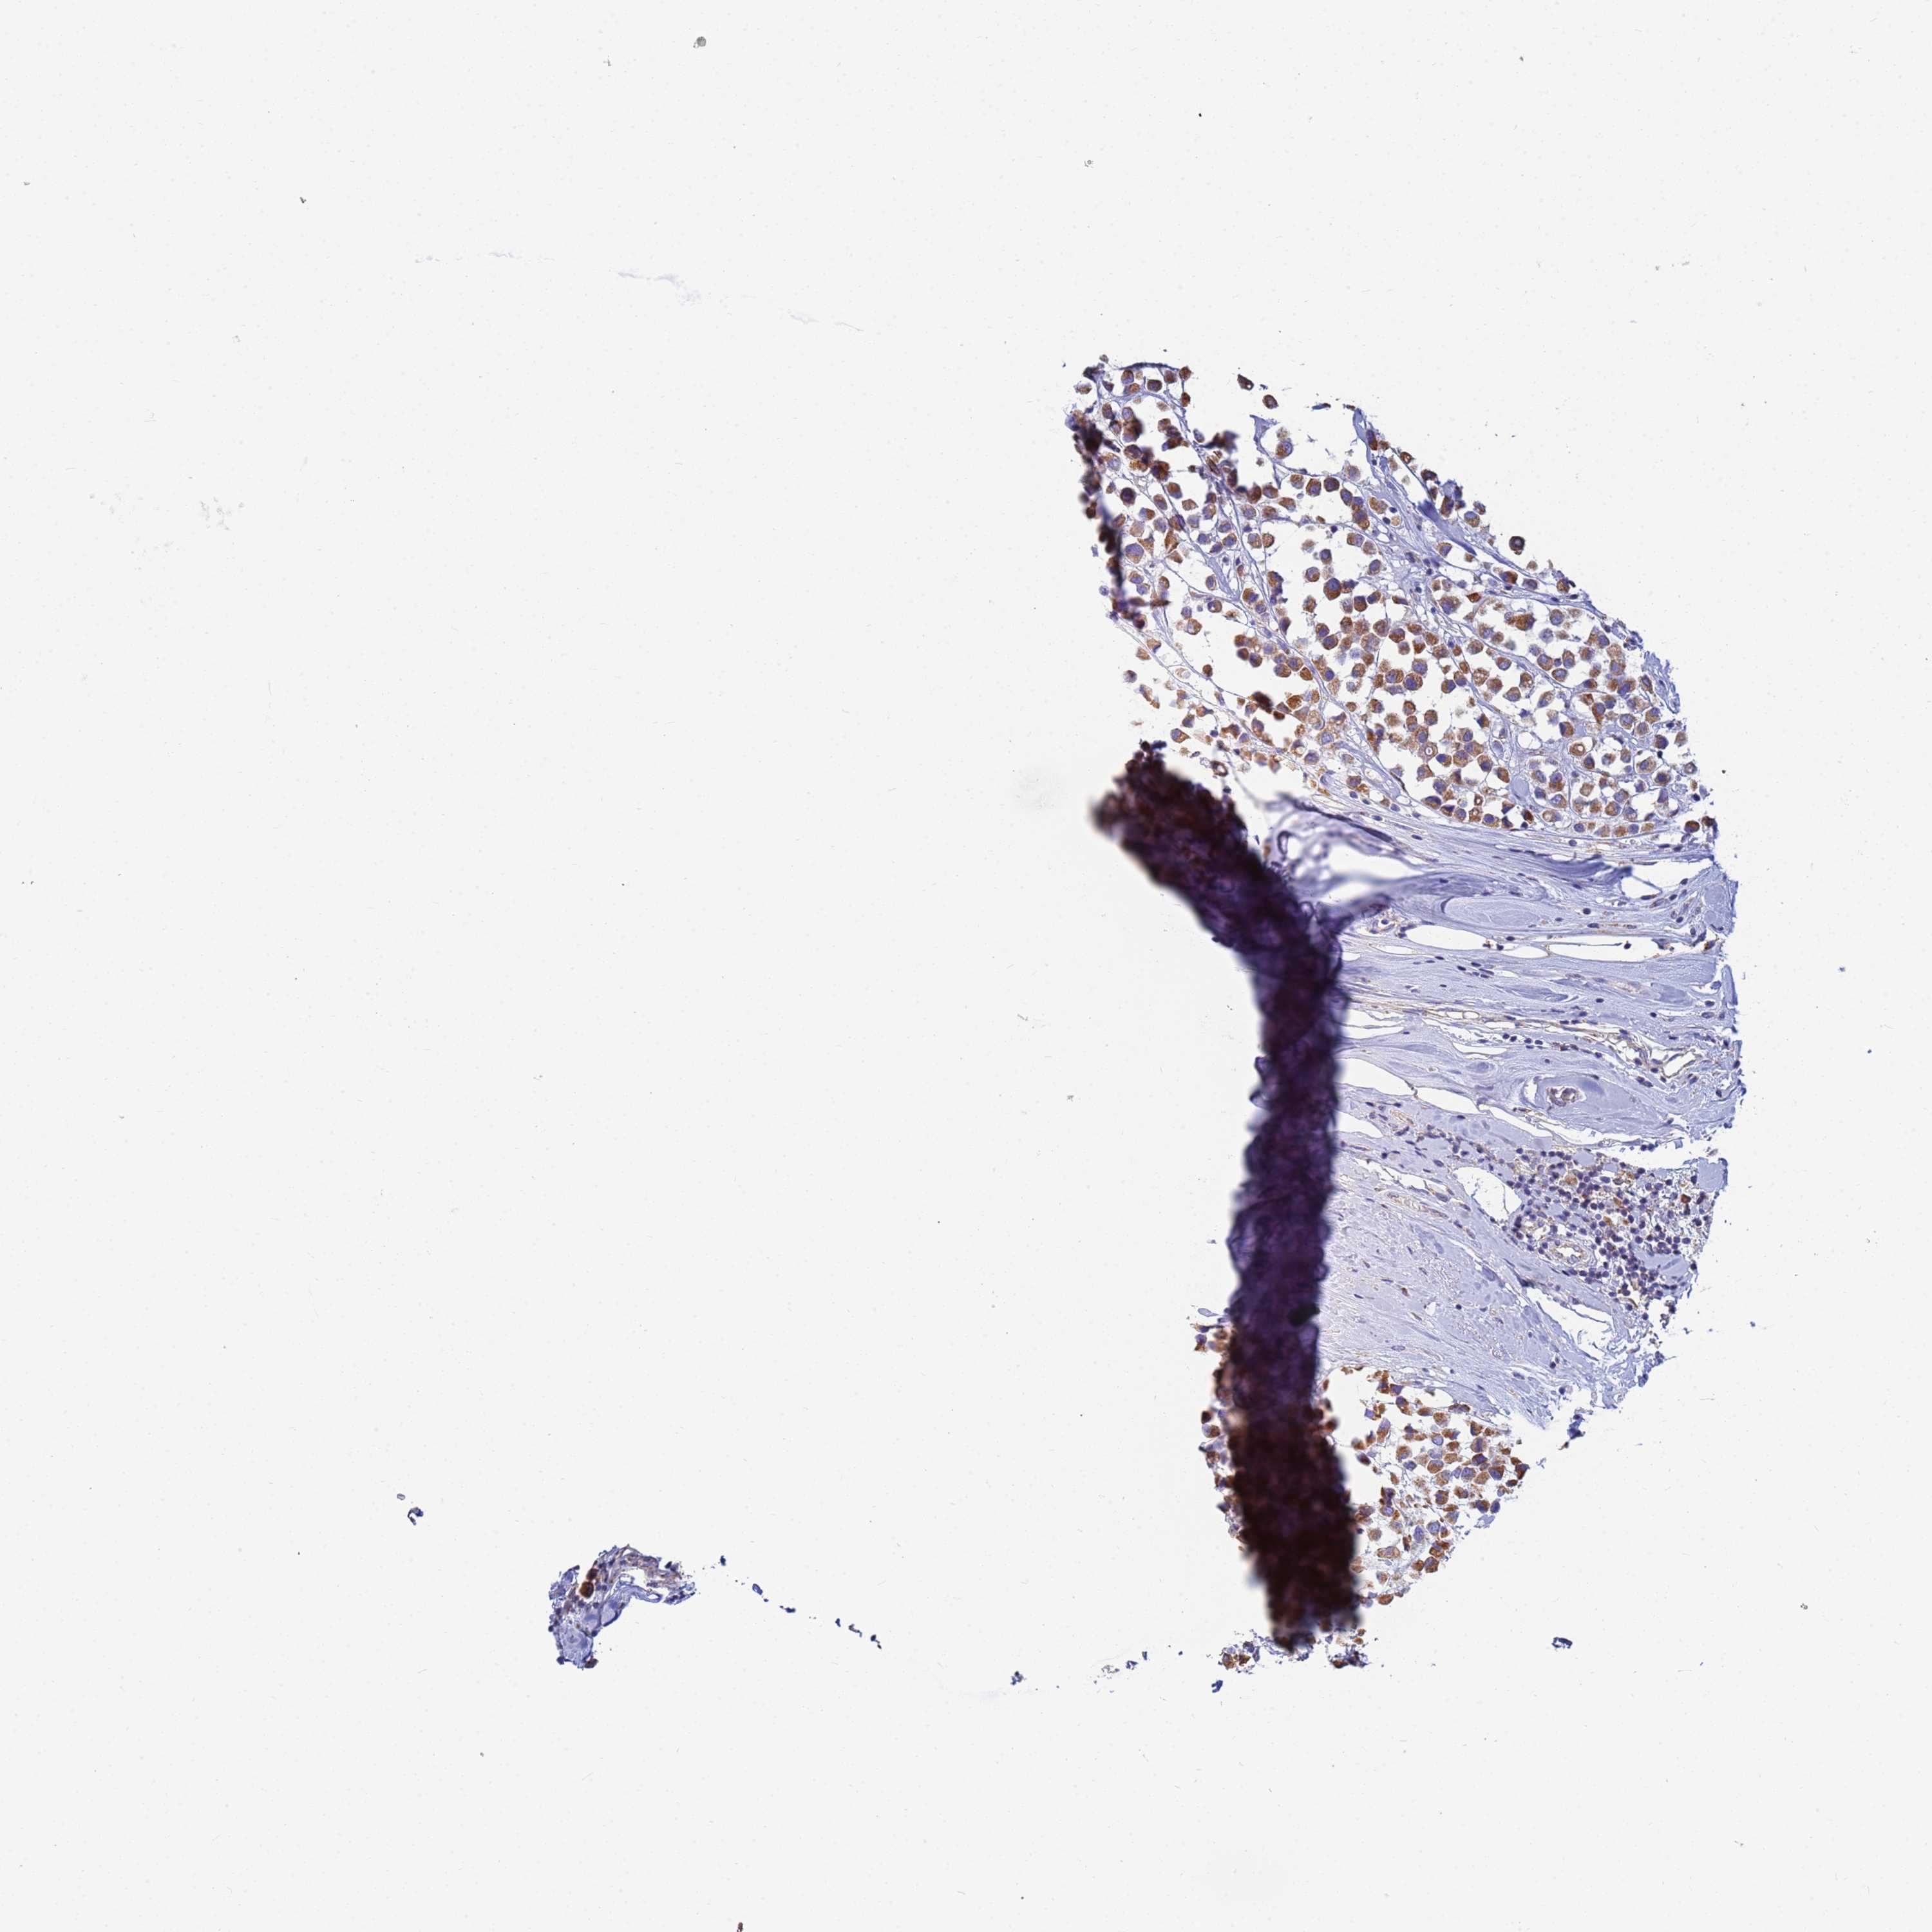

CANCER BREAST CANCER Show tissue menu

BRCA TCGA BRCA VALIDATION PROTEIN EXPRESSION

ANTIBODIES

AND

VALIDATION